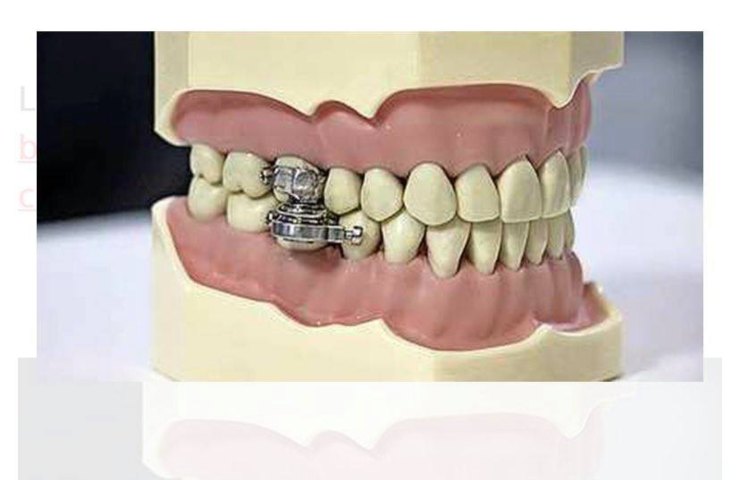

Questo dispositivo è stato inventato dai medici dell’Università di Otago, in Nuova Zelanda, è uno strumento che può essere montato dai dentisti ed è formato da dei bulloni che serrano letteralmente la bocca.

Il dispositivo anti obesità è stato inventato da alcuni scienziati dell’Università di Otago in Nuova Zelanda. Come si vede dalla foto è un vero e proprio bloccaggio della bocca, la cosa ha fatto molto discutere.

Lo strumento può essere impiantato solo da un dentista, viene installato sull’arcata dentale e tramite l’ausilio di alcuni magneti permette l’apertura della bocca solo di due millimetri. E’ possibile bere tramite una cannuccia ma impossibile mangiare.

Lo strumento moderno è considerato da diverse persone come uno strumento per le torture medioevali, questo aggeggio permette una dieta esclusivamente liquida e non solida. Si chiama DentalSlim Diet Control ed è il primo strumento al mondo per quest’utilizzo.